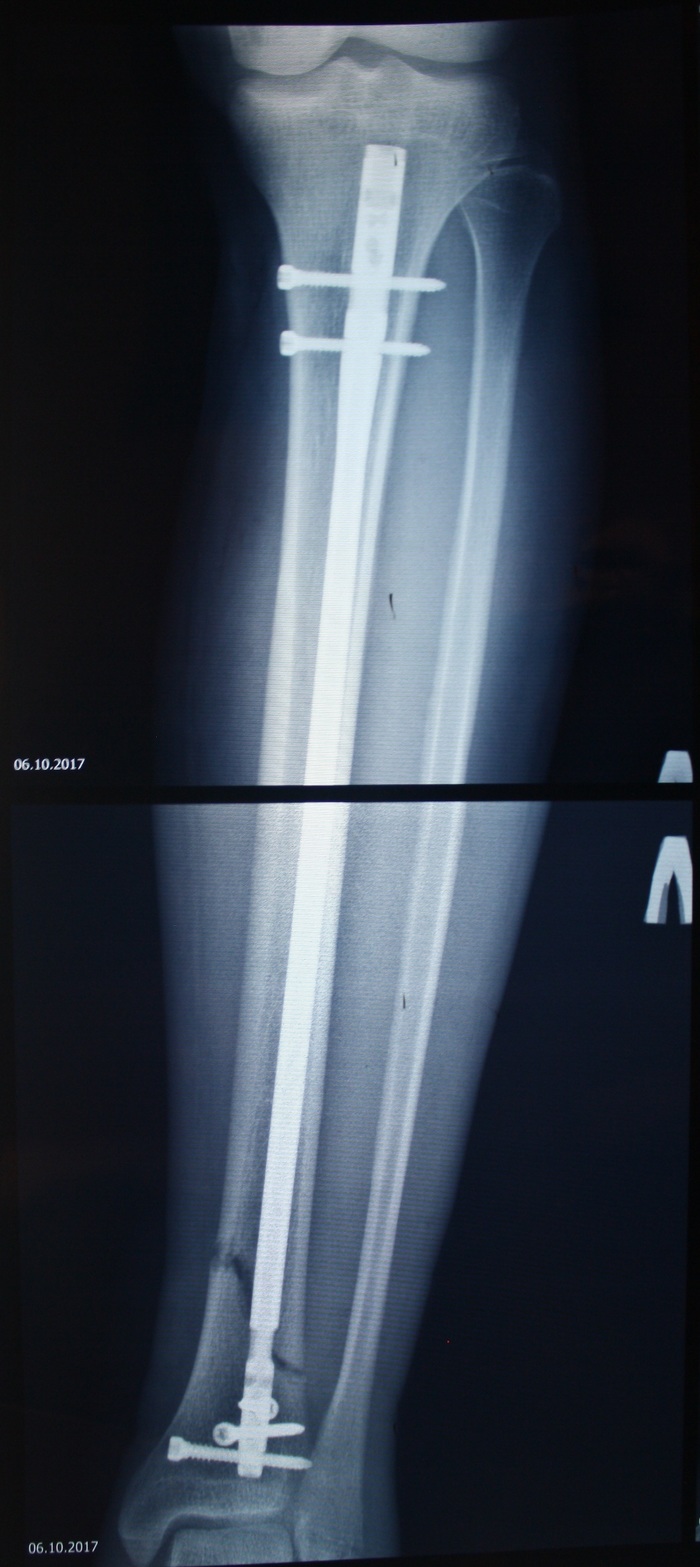

3, 4) Третий и четвертый документ - выписной эпикриз и рентген снимки после операции, их Вам должна выдать больница которая проводила операцию остеосинтеза по выписке. В нем должен быть указан Ваш диагноз, проведенная операция с указанием вида вида импланта (например как в моем случае - Остеосинтез б. берцовой кости левой голени штифтом с блокированием).

Итак в день Х, приезжают за мной с каталкой, предлагают переложить, говорю что я сам, залезаю на каталку, накрывают простыней, дают подписать бумажки на согласие проведения операции, подписываю, отдаю и поехали. На выезде из отделения нас ловит медсестра и без предупреждения вкалывает два укола в бедро, как потом выяснил это был антибиотик и успокоительное. По длинным коридорам едем дальше. Приезжаем, стоим ждем в предбаннике так сказать, прождали примерно полчаса, что так долго не знаю, то ли занята была, то ли хирурги готовились. Заезжаем, меня перекладывают на стол, приходит анестезиолог, спрашивает согласие на проведение спинальной анестезии, соглашаюсь, просит повернуться на бок и согнуться как "замороженная креветка". Еще до операции погуглив о данном виде анестезии выяснил что момент прокола позвоночника не из приятных. Поэтому предупреждаю что от "новых ощущений" могу дернуться (что очень нежелательно, т.к. игла может попасть не туда), делают в месте введения иглы сначала местную анестезию, а потом уже спинальную. Ощущений не было никаких. На все у анестезиолога ушло минуты 2-3. Дальше говорят лечь на спину, ждем пока подействует анестезия. Пока ждем срезают гипс, фиксируют в удобном для хирурга положении ногу, ставят катетер и вешают шторку чтобы от вида проводимых хирургом манипуляций плохо не стало, т.к. при спиналке находишься в сознании. Для контроля действия анестезии периодически просят поднять здоровую ногу, как только не получится - начинают. В принципе дальше почти ничего не видел, только под конец видел изображение на мониторах ЭОПа (типа рентгена, но в реальном времени дает картинку), когда проводили блокирование штифта в нижней части. Периодически анестезиолог заводил разговор и спрашивал как самочувствие. Как мне показалось сверлили совсем немного, видимо только под винты отверстия. Когда все закончили поставили капельницу с физ. раствором и отвезли обратно в палату. По прибытии обратно в палату анестезия еще действовала, врач принес завернутый в полотенце лед и приложил к голени чтобы отек был меньше. Пока капала капельница я решил поспать. Поспал примерно с час-полтора, а когда проснулся тут то меня и ждала боль от всех проведенных манипуляций, по силе была сравнима с болью в момент получения перелома, за все время проведенное в палате с момента прибытия из операционной до момента пока я заснул ночью насчитал 4 укола обезболивающего, я бы не сказал что они сильно помогали. На след. день уже было на порядок легче.

Вот так выглядела нога когда я проснулся утром на след. день:

Дальше в принципе ничего особенного, наблюдение и перевязки каждый день. Со следующего дня после операции можно ходить на костылях приступая на травмированную ногу, при нахождении в любом положении отличного от лежачего требуется бинтование эластичным бинтом от пальцев ноги до колена чтобы отек не увеличился. На 4-ый день после операции выписали из больницы. Суммарно с момента поступления я пробыл 8 дней, на 9-ый выписали.